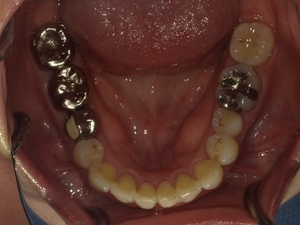

ガタガタとした歯並びや八重歯(叢生)CASE8